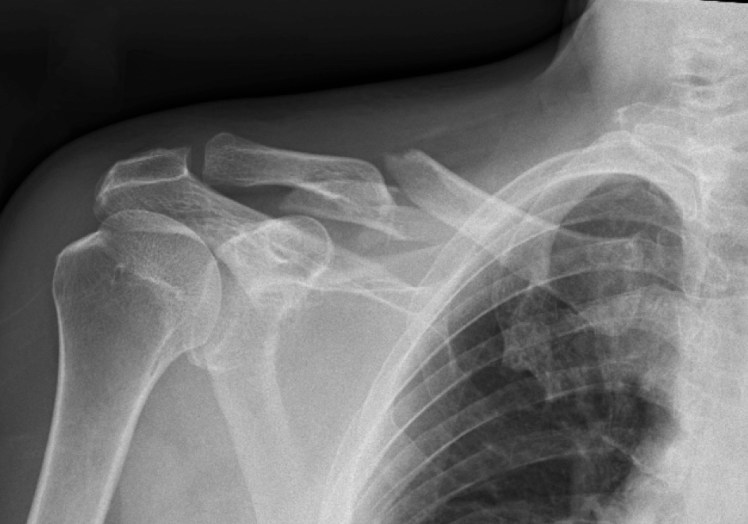

What’s the Diagnosis? Gepost op 11 maart 201811 maart 2018 door netwerkvsseh What’s the Diagnosis? @emdaily.cooperhealth.org Dit delen: Delen op X (Opent in een nieuw venster) X Share op Facebook (Opent in een nieuw venster) Facebook Delen op LinkedIn (Opent in een nieuw venster) LinkedIn E-mail een link naar een vriend (Opent in een nieuw venster) E-mail Afdrukken (Opent in een nieuw venster) Print Vind-ik-leuk Aan het laden... Gerelateerd